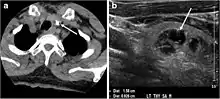

Fig. 2. A 51-year-old female patient post left hemithyroidectomy, with incidentally discovered a right thyroid colloid nodule on CT scan. an Enhanced axial CT scan of the neck demonstrates a well-defined, hypodense right thyroid nodule (white arrow) with no internal calcifications or cervical lymphadenopathy. b Transverse greyscale thyroid ultrasound demonstrates a well-defined, hypoechoic right thyroid lobe nodule with a central echogenicity including comet tail (ring down) artefacts (white arrow). No vascularity (not shown) or calcifications were detected.